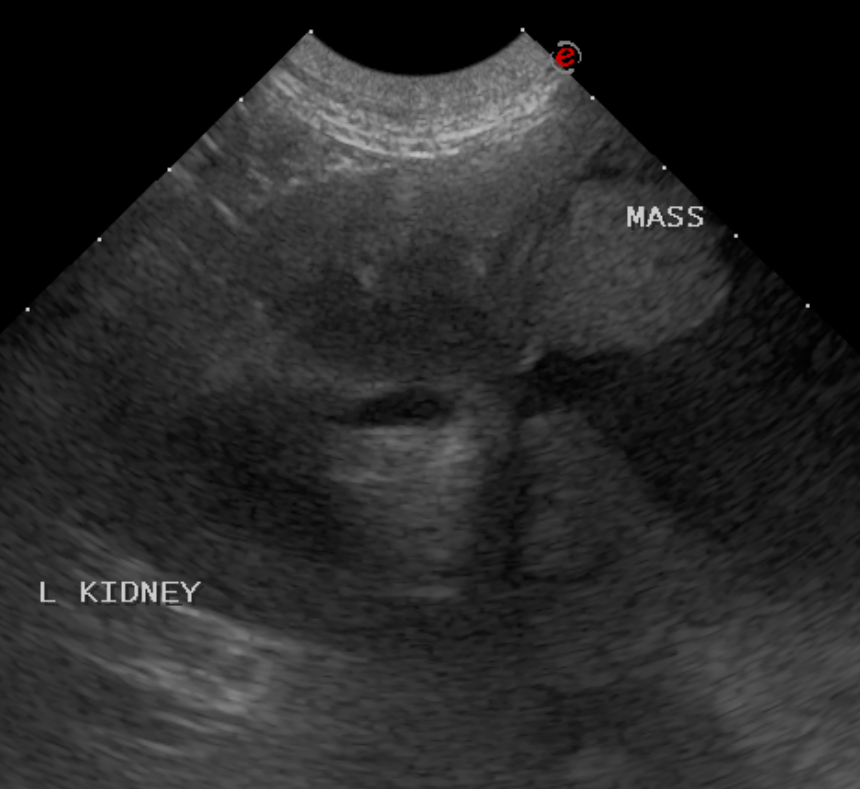

In this patient, the final diagnosis is… a large cystic renal mass! The ultrasound images shows the normal cranial pole of the left kidney with a very large cavitated fluid filled mass extending from the caudal pole.  Only a small portion of the mass is imaged, the overall size was >10 cm.

Ultrasound